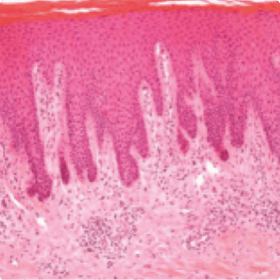

(A) Psoriasis vulgaris characteristically shows acanthosis, parakeratosis, and dermal inflammatory infiltrates.

(B) In pustular psoriasis, acanthotic changes are accompanied by epidermal predominantly neutrophilic infiltrates, which cause pustule formation.

Figure 1. Microscopic and macroscopic features of GPP. Histopathology of psoriasis. (A) Psoriasis vulgaris characteristically shows acanthosis, parakeratosis, and dermal inflammatory infiltrates. (B) In pustular psoriasis, acanthotic changes are accompanied by epidermal predominantly neutrophilic infiltrates, which cause pustule formation. (Reproduced from “Psoriasis Pathogenesis and Treatment” by Adriana Rendon and Knut Schäkel Int J Mol Sci. 2019; 20:1475; http://dx.Doi.org/10.3390/ijms20061475; licensed under CC-BY 4.0). (C) Macroscopic features of GPP. (Reproduced with permission from DermNet New Zealand Trust, Hamilton, New Zealand.)